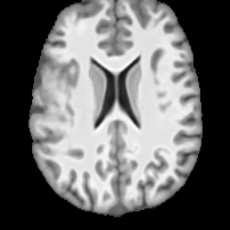

Healthy w/Lesion MaskPathologicalDifferencew/o LCGw/ LCG(a)Refer to captionRefer to captionRefer to captionRefer to captionRefer to captionRefer to captionHealthy w/Lesion MaskPathologicalDifferencew/o LCGw/ LCG(b)Refer to captionRefer to captionRefer to captionRefer to captionRefer to captionRefer to caption

Figure 7: Ablation study of Lesion Consistency Guidance (LCG). Without LCG, the generated pathological regions are indistinct and show weak pathological expression in both examples.

Lesion Consistency Guidance. Fig. 7 illustrates the impact of Lesion Consistency Guidance (LCG) for healthy-to-pathology editing. Without LCG, the generated lesion regions appear blurry around lesion boundaries, and the pathological patterns are less distinct, resulting in ambiguous lesion localization and weak pathological expression. Incorporating LCG produces lesions with more precise localization and well-defined shapes that better align with the given lesion masks, as well as textures and contrasts that exhibit stronger pathological characteristics. These results demonstrate that LCG effectively enforces lesion-aware conditioning, enhancing both spatial and semantic consistency of the generated pathological regions.